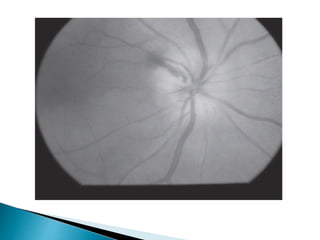

progressive optic nerve cupping with

scotomas).

 Diagnosis aided by presence of risk factors

such as elevated intraocular pressure (IOP),

positive family history, predisposed race,

advanced age and thin central corneal

thickness

 Notching of the rim.

 Verticalization of the optic cup.

 Acquired optic pit.

 Baring of a circumlinear vessel.

 Vessel bayoneting at the optic rim (indicating bean-

pot cupping).

 Nasalization of vessels.

 Disc hemorrhage (Drance hemorrhage).

 Abnormally large or atypical pattern of peripapillary

atrophy (beta zone atrophy).

 Nerve not exhibiting rim pallor.